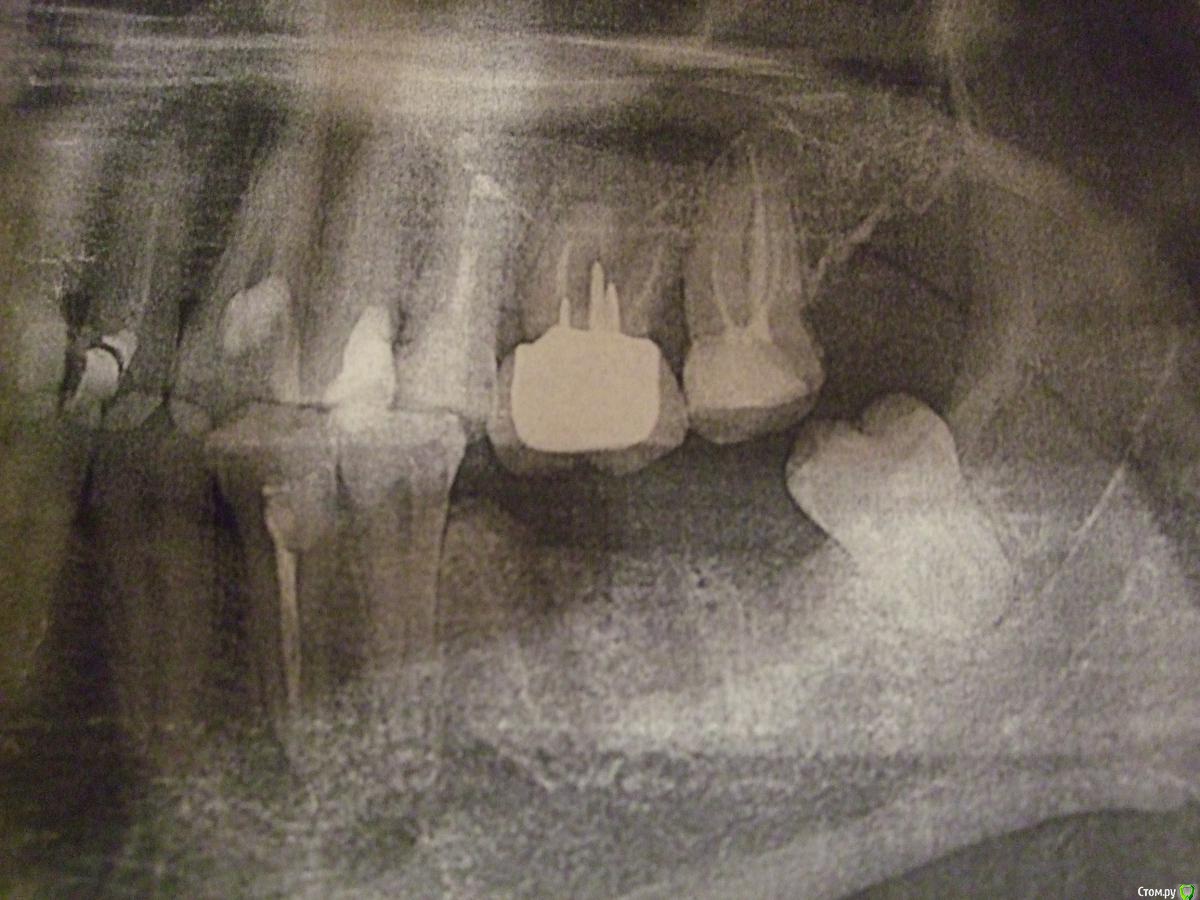

Aliluev Опубликовано 16 декабря, 2019 Автор Поделиться Опубликовано 16 декабря, 2019 приведите тему в соответствие правилам форума http://forum.stom.ru/topic/20613-sovety-patcientam-obiazatelno-k-prochteniiu/, иначе её придется закрытьИзвините, а в чём я нарушаю правила? Готов исправиться. Нужно выложить снимок панорамный, в этом ошибка? Ссылка на комментарий

red_butler Опубликовано 17 декабря, 2019 Поделиться Опубликовано 17 декабря, 2019 Извините, а в чём я нарушаю правила? Готов исправиться. Нужно выложить снимок панорамный, в этом ошибка?да, нужны объективные данные. а то тема скатывается не туда... Хотел бы продолжить тему, если можно.Прошу не обвинять меня в запредельной наивности, просто хотел бы узнать ваше мнение. Ведь моя тема - бюджето, но хорошо сделать импланты.На днях увидел рекламу в одной сети клиник - как раз они за 24900 рублей вместе с металлокерамикой всё включено ставят по акции импланты sgs, о которых я тут на форуме уже прочитал и их не советуют в целом.НО в этой сети есть акционные импланты Nobel и Astra Tech всего за 49900 рублей вместе с циркониевой коронкой и тоже всё включено. В чудеса я не верю. Промониторил цену на такой комплект в разных сетях - ниже 9000 не нашёл. На Стаусман вместе с коронкой из циркония и тоже всё включено всего 60000 рублей. Остем с цирконием всего за 30000 (!). Вообщем на ВСЕ импланты скидки по сравнению со среднемедианной ценой в Москве 40-55%, я подсчитал. Это просто офигенно многоСпросил у них, в чём подвох -ответ был такой примерно: у них дескать оптовые покупки, поэтому так и дешево (вообще-то почти у всех сетей покупки тоже оптовые) и они дескать хотя побольше продать ( все хотят больше заработать).Итак, подвох тут ведь должен быть? Трудно поверить, что у всех производителей имплантов с ними и только с ними эксклюзивные условия поставки.финансовые вопросы на форуме не обсуждаются Ссылка на комментарий

Aliluev Опубликовано 17 декабря, 2019 Автор Поделиться Опубликовано 17 декабря, 2019 Съездил к ним сегодня и побеседовал с их имплантологом. По его словам цена столь низкая на все импланты связаны с низкими закупочными ценами - этим занимаются маркетологи, не он, но за качество он отвечает. "Можете посмотреть номера, все лицензии на материалы". Только я в этом мало что понимаю, так что тут вопрос открытый. Кроме того у них по его словам есть свои мастерские, где они вытачивают коронки (хотя вроде у многих они тоже есть), вот почему цену итоговую можно сильно скинуть. В целом он объяснял всё вроде вполне компетентно на мой любительский уровень. Единственное, что когда я спросил его про разные поверхности у имплантов (а они действительно отличаются немного разной остеоинтеграцией лучшей или худшей в комплексе всех характеристик импланта - у одних поверхность прежнего поколения SLA, а других заявлена как гидрофильная, то есть с улучшенной интеграцией), он уверенно стал утверждать, что поверхность не имеет значения по сути. Что-то сомневаюсь.Я сделал КТ на базе одного из их отделения, диск мне дали. Предложили как вариант сделать на базе независимых центров ренгенодиагностики, но у них немного дешевле. Даже если я не буду делать у них импланты, всё равно эта КТ мне пригодится. Сказали, что вроде везде будет читаться.Ещё спросил про необходимые анализы - сказали, что биохимию делать не нужно, так как у меня только 2 зуба, а общий анализ крови достаточно самый обычный, можно даже не расширенный и даже без СОЭ. Хотя я читал, что СОЭ нужно вроде в любом случае. Не знаю, что тут и сказать. Вечером с ними созвонюсь, узнаю мнение врача насчёт моего КТ. Ссылка на комментарий